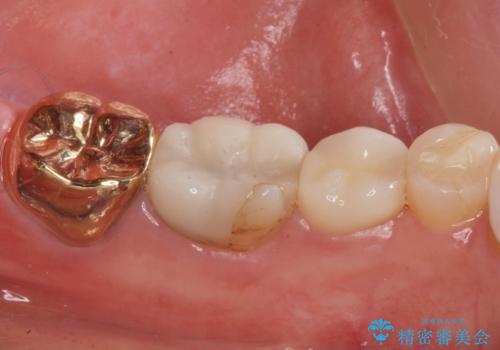

2. 昔いれたクラウンが割れたので金属の被せ物を入れたいの治療中

2.